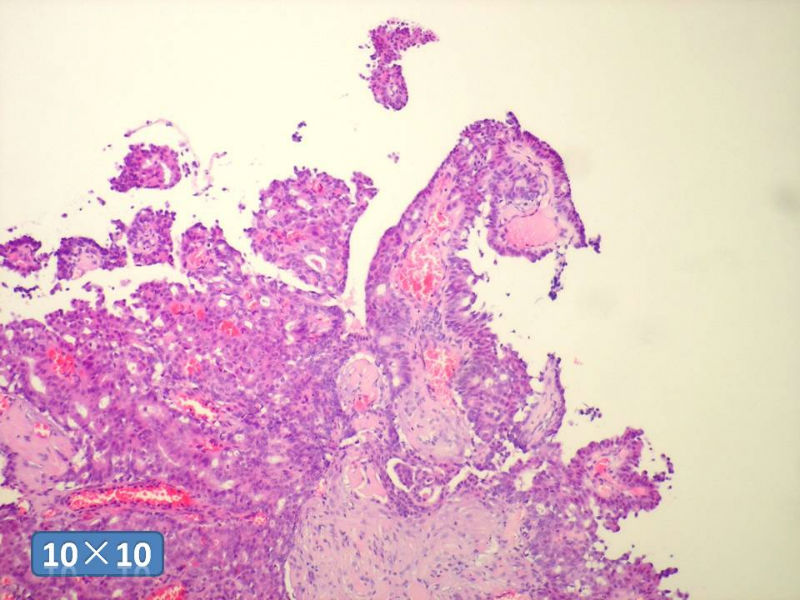

只能说是乳头状瘤

是不是导管内

乳头状瘤 and 导管内乳头状瘤 are the same; Benign lesion.

After you work up and you still cannot be sure it is benign , atypical or maignant lesion, you can call 乳头状lesion.

If this is excisonal case, you should figure out the nature of the papillary lesion.

我的意思就是提醒大家 在不是很确定的情况下 尽量少给自己套枷锁